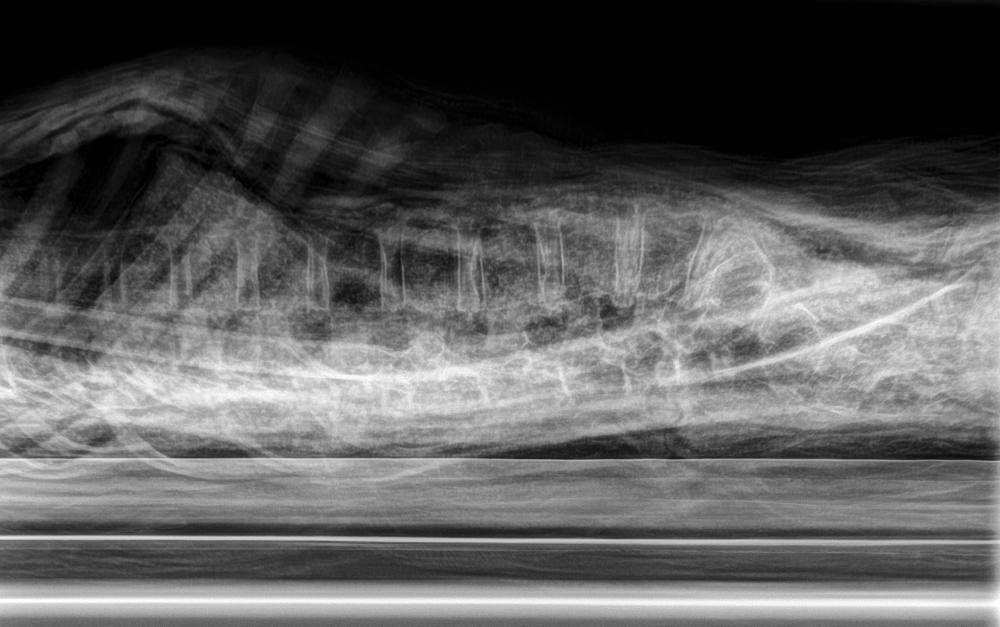

mummy, boy, human remains

- The mummy of a small boy.